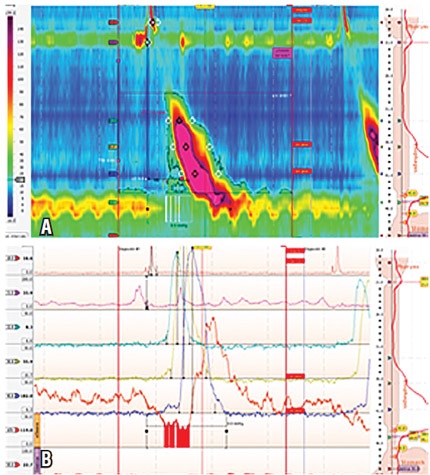

Paciente masculino de 63 años con antecedente de infarto agudo de miocardio en 2014, con compromiso de tres vasos, que se intervino inicialmente con prótesis coronaria y luego con revascularización miocárdica quirúrgica con dos puentes coronarios, quien consultó por persistencia de dolor torácico de características atípicas, acompañado de sensación de disfagia para sólidos sin impactación alimentaria. Estudios por cardiología descartaron origen cardiogénico. Se decidió realizar EVDA, la cual fue normal, por lo que se realizó MAR y se encontró 1 de 10 ondas con un ICD de 8351 mm Hg/cm/s. Las demás ondas tenían un ICD mayor a 5000 mm Hg/cm/s (tablas 1 y 2; figura 1).